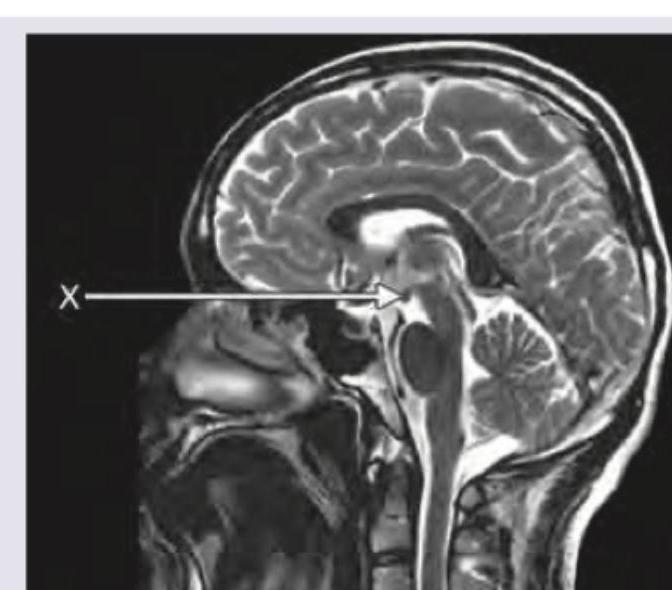

Which is the structure marked here?

Explanation: **Pons** - The image provided is a **sagittal view of an MRI of the brain**, and the arrow labeled 'X' points directly to the pons, a key part of the **brainstem**. - The pons is characterized by its **bulbous shape**, located anterior to the cerebellum and superior to the medulla oblongata, clearly visible in this anatomical plane. *Corpus callosum* - The **corpus callosum** is a large, C-shaped nerve fiber bundle found beneath the cerebral cortex and connects the two cerebral hemispheres. - It is located **superior to the structure indicated** by the arrow in this sagittal view. *Mammillary body* - The **mammillary bodies** are a pair of small, rounded prominences forming part of the posterior hypothalamus. - They are located **anterior and inferior to the region indicated** by the arrow. *Pineal gland* - The **pineal gland** is a small endocrine gland that produces melatonin and is located in the epithalamus, near the center of the brain. - It is situated **posterior and superior to the structure indicated**, typically nestled between the superior colliculi.